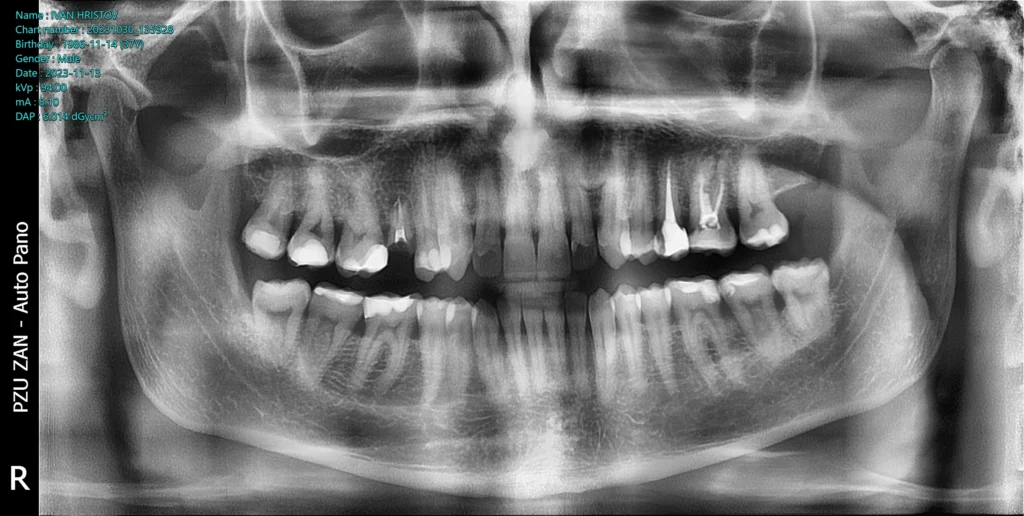

This patient came to our office with a broken upper second premolar that could no longer be saved. The damage was extensive, and the tooth had no long-term prognosis, making extraction the only viable option.

After a thorough clinical evaluation, we determined that a dental implant would be the best solution to restore both function and aesthetics. The goal was to achieve a natural-looking result while preserving the surrounding bone and tissues.

We began with detailed CBCT 3D imaging and careful digital planning. This allowed us to map out the exact position, angle, and depth of the implant before the procedure even began.